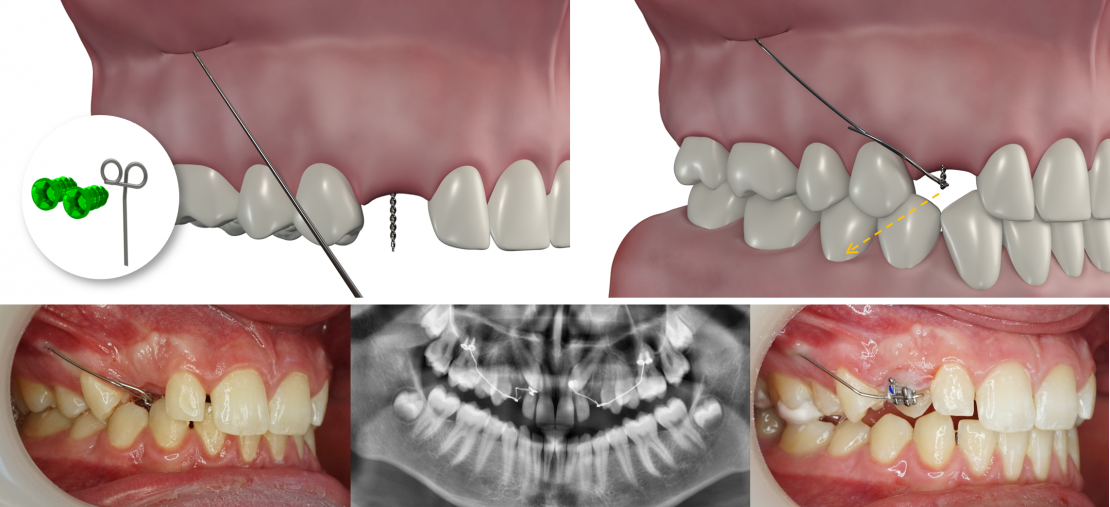

Site d'implantation

Kit Traction de canine incluse (2 vis + 1 CT8-1 droit ou gauche)

NB : respecter le côté droit / gauche

Processus zygomatique

Mécanique

Le dégagement chirurgical de la couronne de la canine incluse vient d’être réalisé, la ligature accrochée au bouton collé à sa surface émerge à son emplacement naturel d’éruption.

Le lambeau d’accès à la canine a été refermé et suturé.

Le bras du CT8 est activé vers le bas pour une canine vestibulaire, vers l’extérieur pour une canine palatine. Il est replié sur lui-même et accroché à la ligature reliée à la canine au niveau de son espace naturel d’éruption.

Les deux seules actions à réaliser par la suite seront :

1. Le raccourcissement de la ligature au fur et à mesure du déplacement de la canine.

2. Le contrôle de la direction de la traction et son réajustement éventuel lors de la même opération.